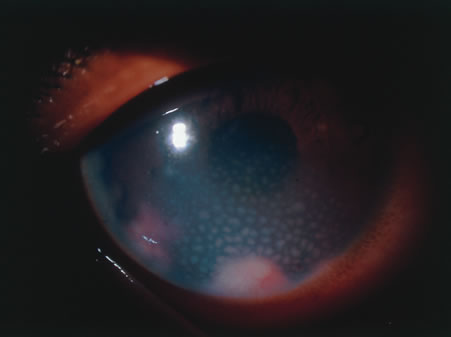

In primary ocular HSV infections, a severe follicular conjunctivitis with regional adenopathy is present. Vesicles may appear on the eyelid skin or lid margin, producing blepharitis (Fig. 3). Corneal involvement initially takes the form of a superficial punctate keratitis, which may progress to dendritic or geographic ulceration. Stromal infiltrates and uveitis are less common and relatively mild in primary disease. In uncomplicated cases, lesions usually heal completely in 2 to 3 weeks without scarring. Most cases of ocular HSV are recurrences. Recrudescent ocular herpes may take the form of dendritic or geographic ulcers, recurrent erosions, interstitial or disciform stromal keratitis, and anterior uveitis.3 HSV may also be an agent of retinitis and acute retinal necrosis (Fig. 4).